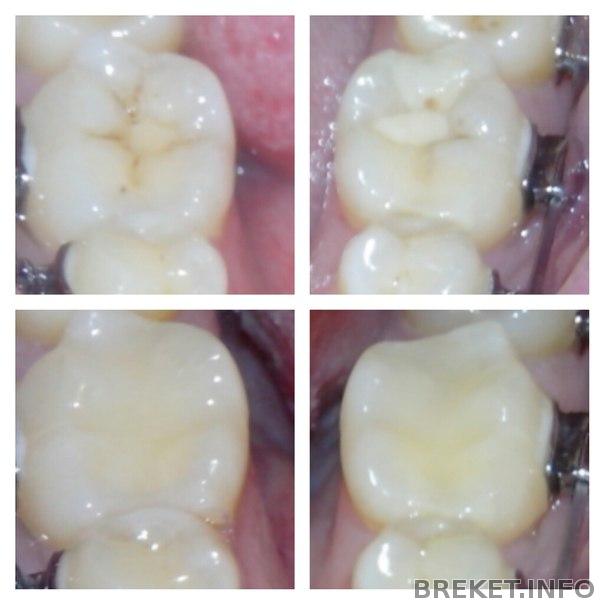

В общем все 3 моих пломбы теперь красивые. Самые страшные сфоткала:

Угу. Вот они тоже считают, что это просто пятно. А в итоге там такой процесс идет. Мне такие дыры нахреначили и светокомпозитом слепили бугры. Мне кажется сейчас от зубов всего процентов 40. Остальное все пломба